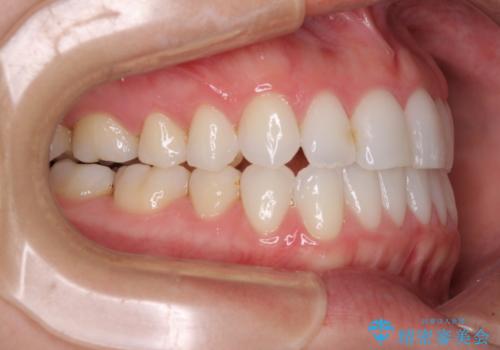

- 前歯のデコボコとクロスバイトを治したいとのことで来院された患者様です。

上下顎ともに歯列全体の側方拡大とIPR(歯と歯の間を削る)によってデコボコとクロスバイトが解消するように設計し、インビザラインにより治療を行うこととしました。

下顎骨の左側への骨格的なずれが強く、上下の正中の位置合わせや奥歯の咬み合わせ構築に苦労しました。